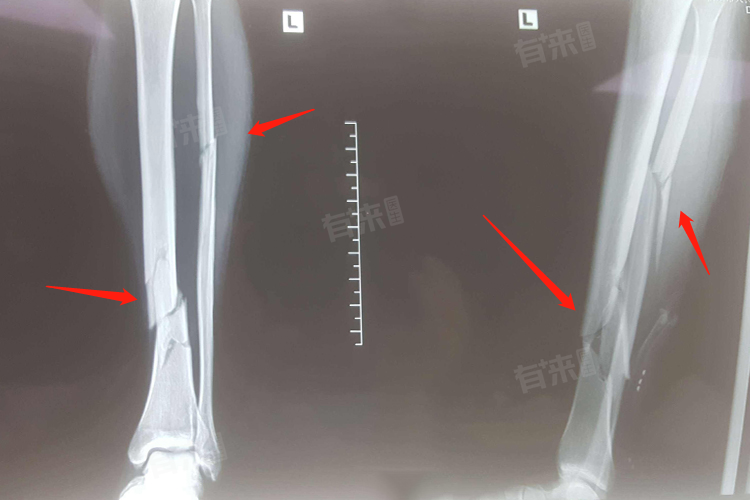

- 骨折缺血段容易发生缺血坏死,影响愈合,如股骨颈骨折,可能损伤相应的血管,导致骨折部位血供不足,从而延缓或阻止骨折愈合。特殊部位的骨折,如手部和足部舟骨骨折、距骨骨折或胫骨下段骨折,由于血液循环相对较差,也容易出现不愈合。

- 骨折端之间的接触是骨折愈合的必要条件,骨折端接触面积越小,越容易发生骨折不愈合。内固定或外固定后,如果骨折端仍存在微动或异常活动,也会影响愈合。此外,骨折断端间嵌夹较多软组织、开放性骨折骨块丢失或清创时去除的骨片较多,都会造成骨缺损,进而影响愈合。